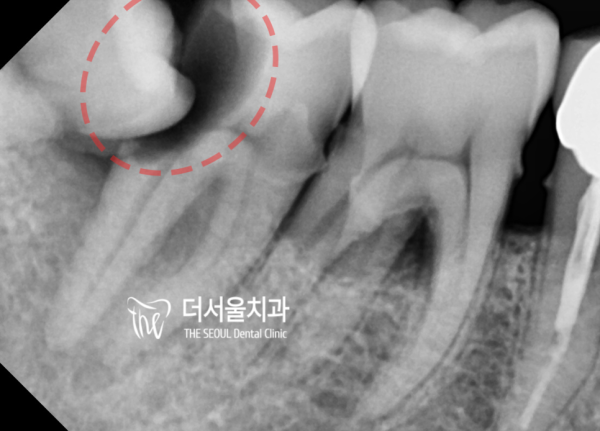

많은 환자분들에 사랑니를 꼭 뽑아야 하는지 궁금해 하시는데요.

사랑니는 통상적으로 양치질이 잘 안되기 때문에 충치가 생기기 쉬운데,

단순히 사랑니만 충치가 생기는게 아니라, 인접한 어금니까지 영향을 주게됩니다.

심한경우에는 사랑니 뿐만 아니라, 앞에있는 어금니까지 발치하고 임플란트를 해야하는 경우가 생깁니다. ㅠㅜ

성남치과 더서울치과를 찾아주신, 이 환자분은 어금니의 통증으로인해 저희 치과를 찾아주셨습니다.

엑스레이를 보면, 양쪽 아래 어금니쪽이 문제가 있습니다.

한쪽은 사랑니때문에 충치가 생겨, 그 앞의 어금니가 거의 절반이 썩어있는 상태이고

사랑니가 없는쪽는 골 파괴 증상이 있어 염증이 가득 있습니다.